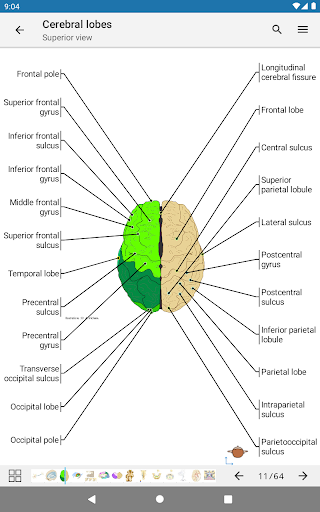

* تحسين عرض التفاصيل للأجزاء التشريحية لتسهيل التعرف عليها في صور الوحدات الحالية والوحدات الأخرى.

- يتميز وضع الدبابيس بسلوك جديد يسمح لك باتباع بنية تشريحية بسهولة أكبر

- يمكنك الآن تحديد حجم الخط الذي تفضله يدويًا لتسميات الهياكل التشريحية (في وضع الملصقات)

- ضمن عرض التفاصيل للبنية التشريحية ، يشير الدبوس الآن إلى البنية ذات الصلة في جميع الصور الحالية